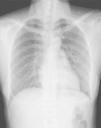

Saturation was maintained at approximately 99% with the oxygen cannula at 2L/min. Physical examination showed palpable subcutaneous emphysema involving the submandibular region, anterior and lateral aspect of the neck, as well as the bilateral supraclavicular regions. There were minor inflammatory signs but there was no local dental infection. Chest radiograph showed pneumomediastinum and subcutaneous emphysema in the neck region (Fig. 1). A computed tomography scan was performed that showed: emphysema extending from the mandibular region to the mediastinum (Fig. 2A and B), as well as the presence of pneumopericardium and left side pneumothorax (Fig. 3A and B) The laboratory tests showed slightly elevated white counts 12400/μL without shift-to-left. The band form was 4% and the segmented form was 80% of total leukocytes. C-reactive protein was 7.4mg/dL. After treatment with a second-generation cephalosporin administered intravenously along with oxygen and oral non-steroid anti-inflammatory drug, the fever subsided within 24h after admission and the symptoms resolved. The patient was discharged 4 days later. After discharge, the patient took oral first-generation cephalosporin for an additional five days. She had a complete clinical and radiological recovery without recurrence of disease (Fig. 4).